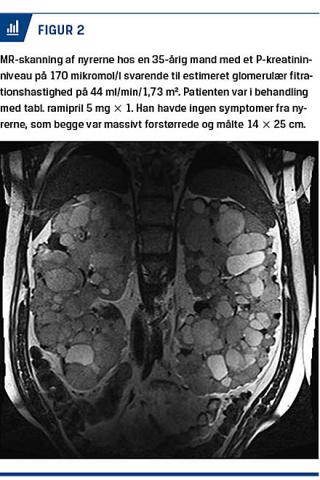

Den er karakteriseret ved tilstedeværelsen af multiple væskefyldte cyster i begge nyrer (Figur 1 og Figur 2). Cysterne vokser med tiden i både antal og størrelse, hvilket resulterer i forstørrede nyrer, hypertension og ofte kronisk nyreinsufficiens. På verdensplan er ADPKD af denne grund den fjerdehyppigste årsag til dialysekrævende nyresvigt [2, 3] og ses i Danmark hos 8% af alle patienter, der får dialyse [4]. Sygdommen fører ofte til dialyse eller transplantation inden 60-årsalderen. Med en estimeret prævalens på 1:1.000 [5] anslås der at være ca. 5.000 personer med sygdommen i Danmark; mange af dem er formentlig udiagnosticerede.